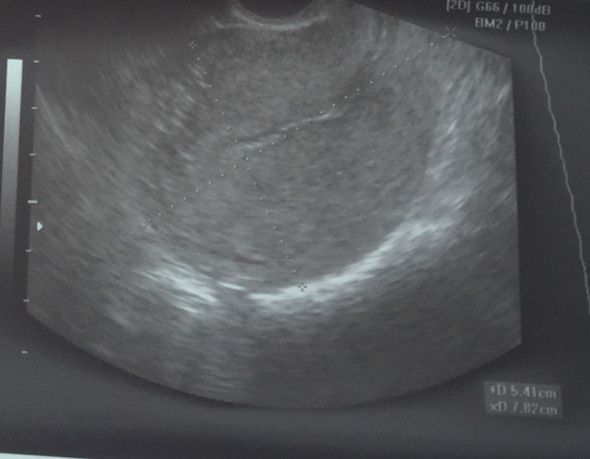

Ultraschall Nach Ausschabung Arzt Schwangerschaft Frauenarzt